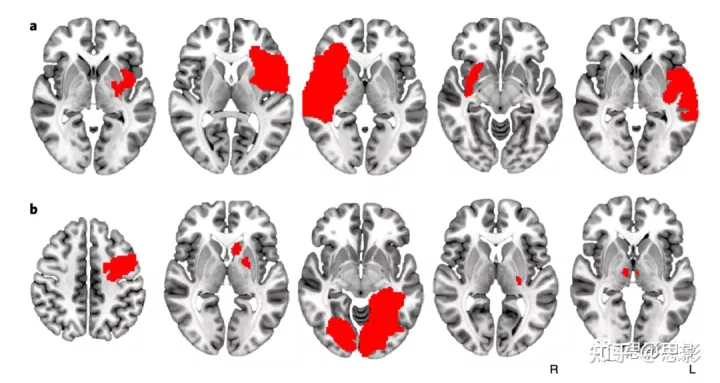

图1:与成瘾缓解相关的病变发生在许多不同的大脑位置。

一些与吸烟成瘾缓解相关的病变与岛叶相交(a),但许多其他病变则没有(b)。每个切片代表不同的患者,病变位置以红色显示。所有129例患者的病变如补充材料图1所示。

图 S1:吸烟者队列病变。

导致吸烟成瘾缓解的病变(A,n = 34)。未戒烟患者的病变(B,n = 69)。戒烟但未缓解的患者的病变(C,n = 26)。每个切片代表不同的患者。组间的病变大小没有差异(单因素方差分析,F = 1.78,p = 0.17)。